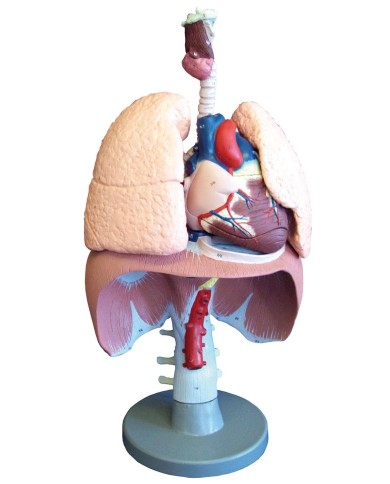

Kit composto da 3 modelli

Su Base, staccabile

Con scheda descrittiva dettagliata

Questo modello dettagliato mostra, oltre alle strutture anatomiche del cuore, anche una parte del diaframma (base)